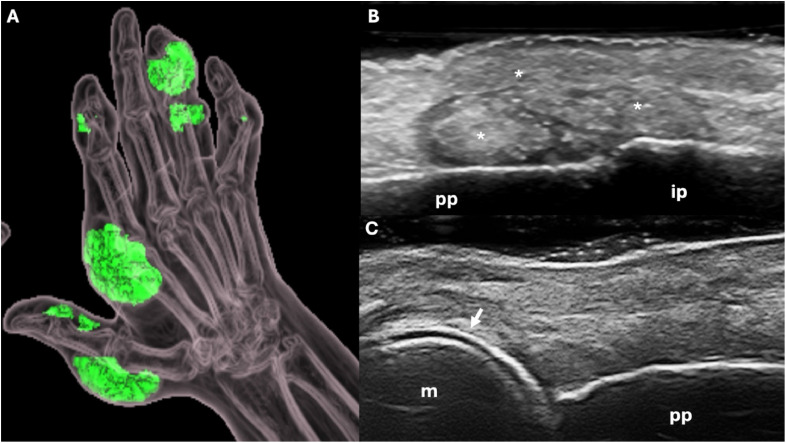

Gout is the commonest form of inflammatory arthritis. Flares are the commonest presentation of gout. Typically, gout flares present as acute monoarthritis, and most often affect the first metatarsophalangeal joint ('podagra'). Other joints in the lower limbs are affected more often than those in the upper limbs. Joint aspiration followed by examination of the synovial fluid using a polarised light microscope is the gold standard for a definite diagnosis of gout. Gout may be diagnosed without recourse to joint aspiration if there is podagra, elevated serum urate and no suspicion of infection. Ultrasonography and dual energy computed tomography may be used to diagnose gout if joint aspiration is unsuccessful or not feasible. Oral colchicine, NSAIDs and glucocorticoids have similar efficacy for controlling gout flare with differing adverse effect profiles. Consequently, the drug choice depends on comorbidities and patient preference.